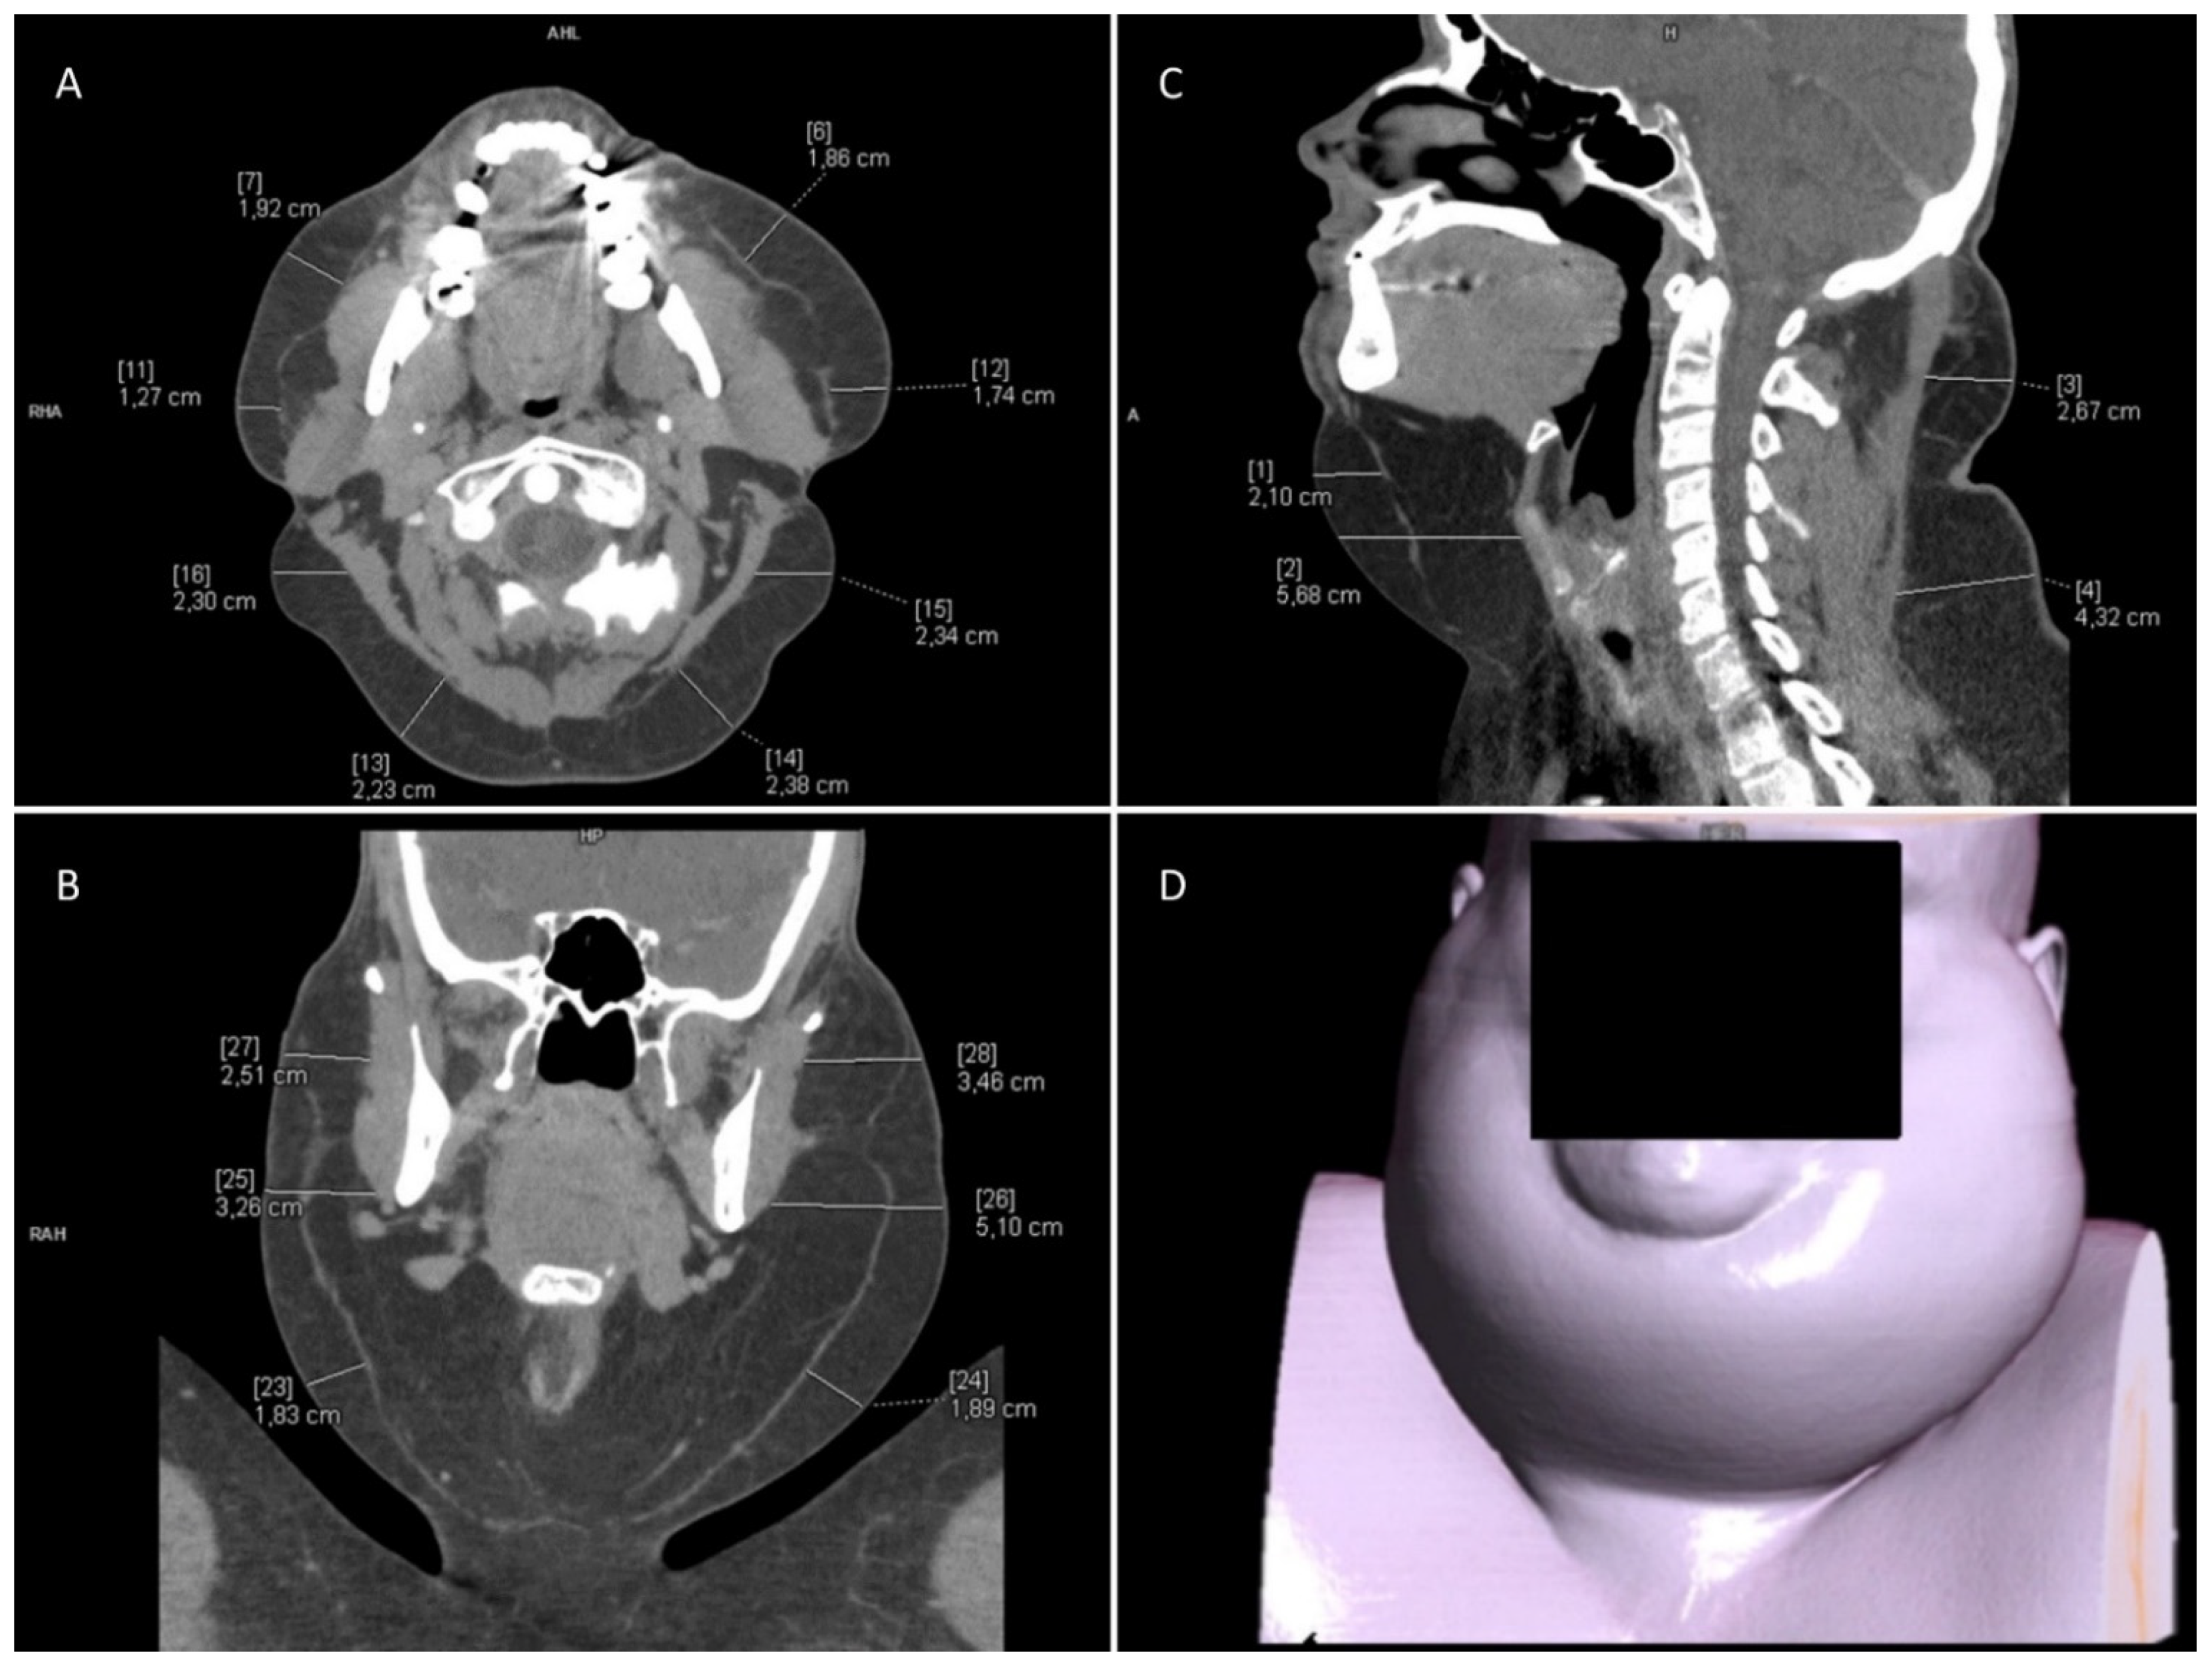

| Neck CT | |

|---|---|

| Exact Location | Fat Layer Thickness [mm] |

| left side of the neck | 50 |

| right side of the neck | 50 |

| chin area | 70 |

| infrahyoid region | 60 |

| right neck triangle | 40 |

| left neck triangle | 30 |